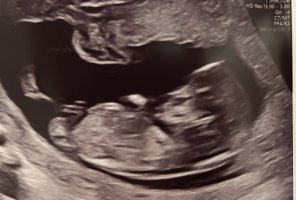

Usikker på om det er nub man ser?13+2 noen som har en tanke her? Synst selv nubben her er mye flatere enn med gutten jeg har

Jeg spurte flere sider, men ene sa at de ikke ville si noe da bare en liten del av Nuben visste så det var vanskelig å si noe om kjønn..Usikker på om det er nub man ser?

Dette er kanskje Nuben?Usikker på om det er nub man ser?

Du hadde rett! Det var navlestrengen. Ingen nub på bildet.Usikker på om det er nub man ser?